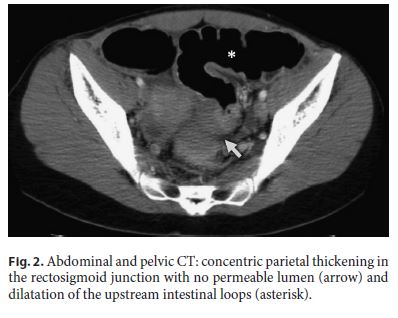

A 30-year-old female was admitted to the emergency department presenting with a 4-day history of sudden onset of abdominal distention, diffuse and moderate colicky abdominal pain, vomiting, and no gas or stool passing. She had no past medical history and was not taking any drugs. On physical examination, she had a distended and tympanic abdomen, slightly painful to palpation, without signs of peritoneal irritation. The vital signs and laboratory tests were within normal values. The abdominal X-ray showed exuberant colonic distention and a stop sign in the rectosigmoid junction (Fig. 1). An abdominal and pelvic computed tomography (CT) identified a concentric parietal thickening in the rectosigmoid junction with no permeable lumen and dilatation of the upstream intestinal loops (Fig. 2).